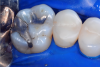

Fig 4. Palatal view of the tooth before the restoration.

Figure 4

In this case, a female patient presented with an asymptomatic tooth that had an incomplete fracture on the distal palatal cusp and potentially the distal buccal cusp.1 The patient was highly motivated to avoid extensive dentistry and had "dead jaw syndrome" from a history of using bisphosphonate medication (Figure 1 through Figure 4). The solution was to perform a composite overlay on the tooth.

To begin this Class II restoration, the first step was to completely remove the old restoration and properly prepare the overlay. In this case, there was an incomplete fracture of the distal buccal cusp and underneath the distal palatal cusp. Although the tooth structure was cracked, it was not desirable to amputate the fracture because the tooth structure itself was good, so the plan was to treat it as buildup material.1 Building a good contact is one of the most crucial steps to ensuring the final restoration is successful.

Throughout this restoration, an infinity edge was placed that would cover most of the tooth and create a crown-like outcome. Even though the dentin in the tooth was healthy, it was also dark, which means there was concern that it might show through the translucent nature of most traditional bulk fills (Figure 5). However, the bulk-fill restorative used was designed for posterior restorations and featured increased opacity for improved esthetics. The B1 shade was brighter and significantly more opaque than the previous bulk-fill materials on the market. Adverse solutions that may have been used in the past, such as applying an opaquer or cutting away the healthy dentin, were no longer required to achieve a more esthetic final restoration (Figure 6).